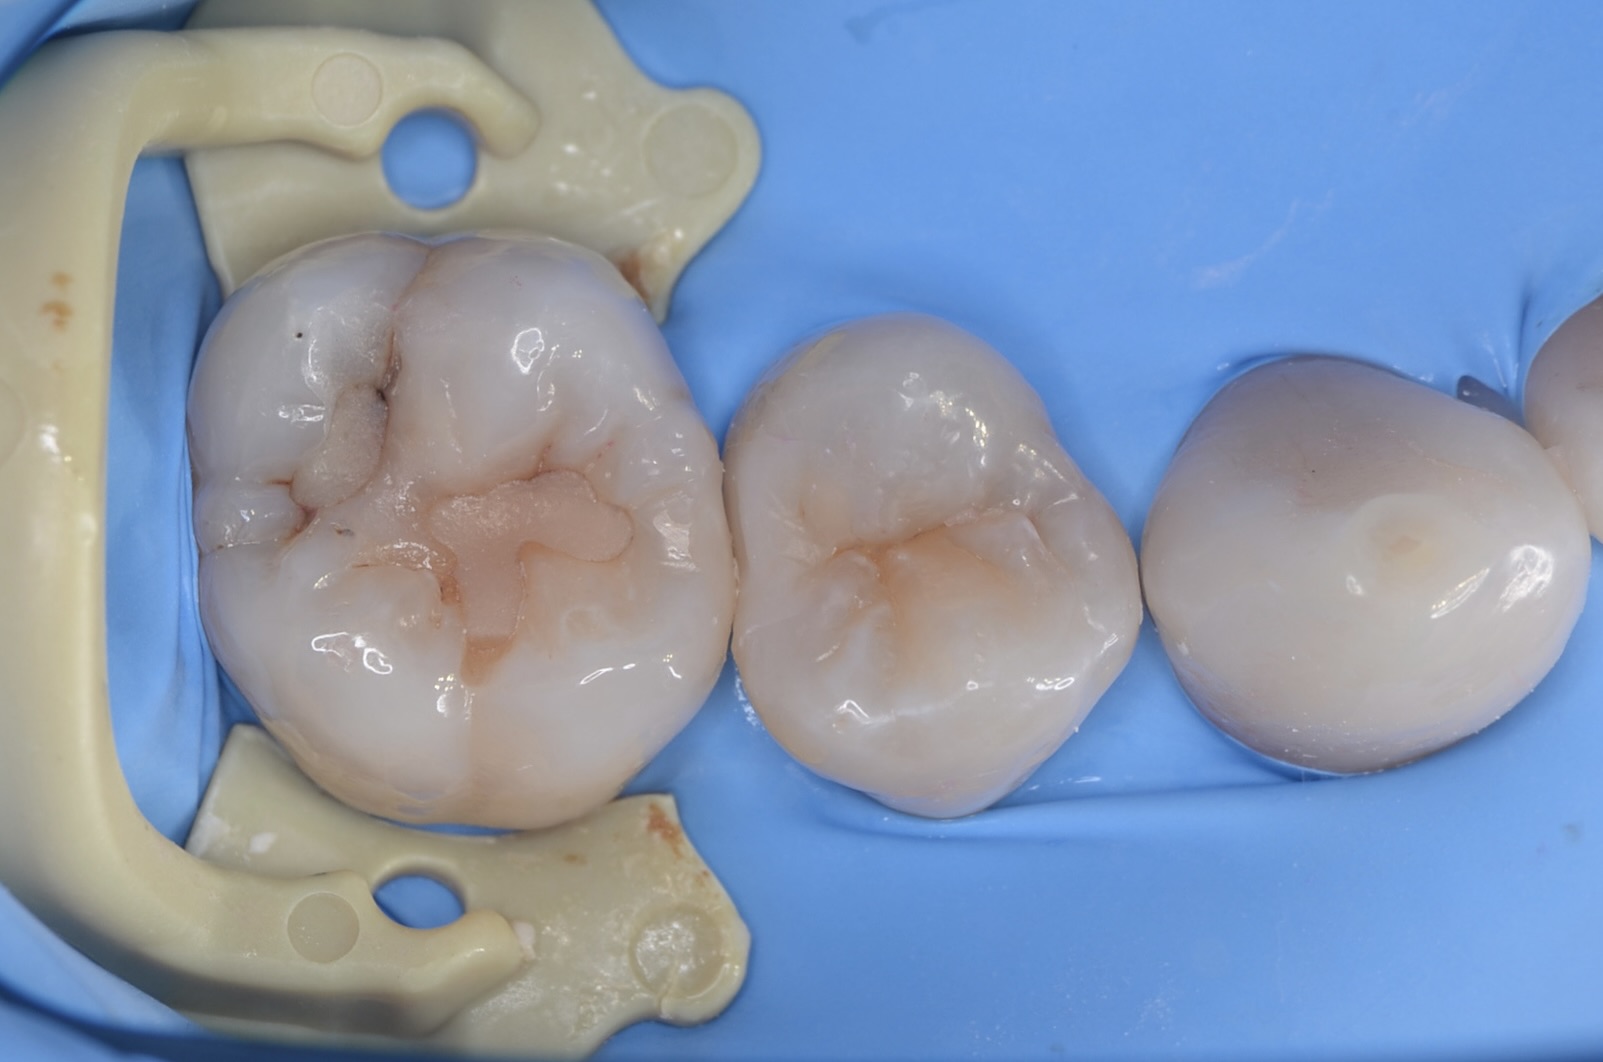

Before

ラバーダム装着&歯間離開

虫歯治療においてもラバーダム装着は必須です。 唾液や血液から歯面が汚染されるのを防ぎ、乾燥状態を保つラバーダムは、接着力を向上させるためにも大切なアイテムです。 セパレーターという歯間離開器で強制的に歯間を1ミリほど広げて目視で虫歯の有無を確認します。 -

歯と歯の間の充填終了

充填後、フロスを歯間部に通して引っ掛かりや適切な接触強さを確認します。 -